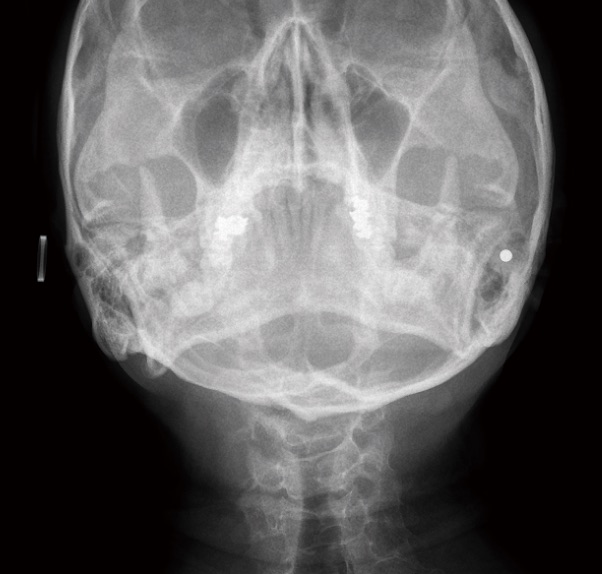

ウォーターズ法撮影